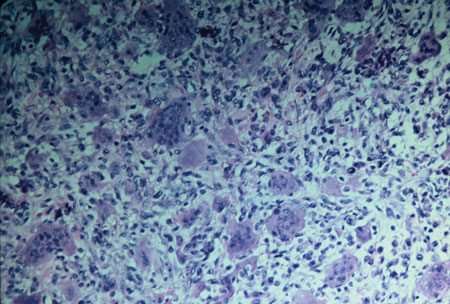

Figur 2

signifikanta mikroskopiska egenskaper: CGCG är känd för de många multinucleated jätteceller som finns i vävnadsprovet. De multinukleära jättecellerna ligger inom ett hav av spindelformade mesenkymceller och finns i blödningsområden.

jättecellerna kan variera i storlek och antal med spridd placering, eller de kan koncentreras inom olika områden av provet. Nybildat ben kan också vara närvarande i provet. Den mer aggressiva typen av CGCG kan inte särskiljas från den icke-aggressiva typen genom mikroskopisk undersökning (se Figur 2).